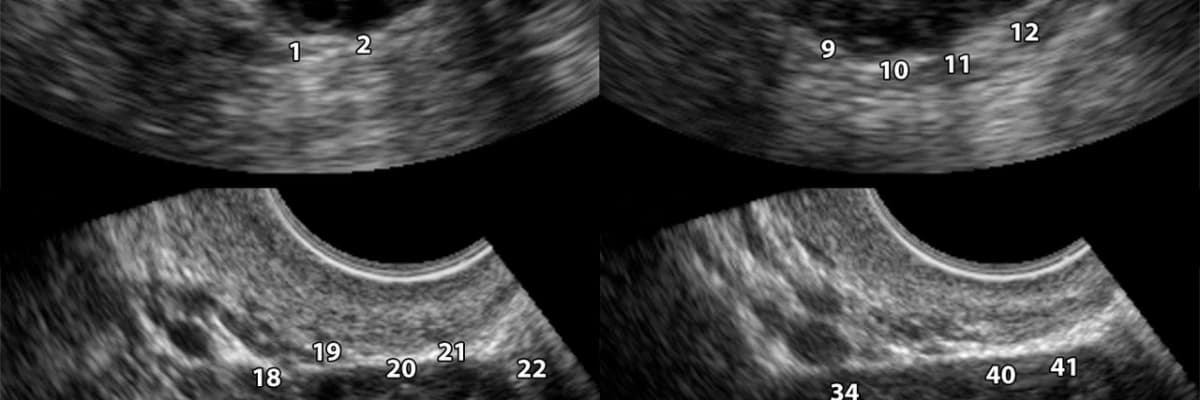

Polikistik Over Sendromu sık görülebilen bir durum. Yumurtalıklarda çok sayıda küçük kistler var. Bu kistlerin çokluğu veya kistlerin salgıladığı hormonlara olan duyarlılık kişideki problemlerin/ belitilerin boyutunu belirler. Bu kistlerin kanserle ilişkisinin olmadığı da bilinmeli.